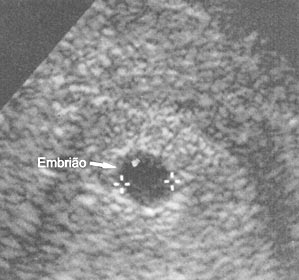

Gravidez 5 semana em diante.

Semana 5 Reprodução O bebê já tem de 5 a 6 mm, é do tamanho de um grão de arroz e os órgãos começam a se formar.” O bebê Já se pode falar em um ser humano, apesar dele ainda estar no período embrionário. O bebê tem de 5 a 6 mm, o que corresponde a um grão de arroz. Os órgãos começam a se formar.